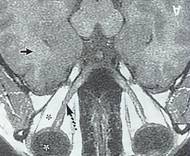

-rezonanţa magnetică nucleară utilizată îndeosebi pentru studiul substanţei nervoase centrale; principiul ei constă în emisia unui puls magnetic puternic către ţesutul ţintă şi analiza semnalului primit de la acesta (deci nu se iradiază pacientul cu razeX ca în cazul tomografiei) şi imaginile obţinute sunt prezentate tot ca nişte secţiuni în tonuri de gri; această metodă diagnostichează cu precizie scleroza în plăci, o afecţiune în care se pierd porţiuni din teaca de mielina care înconjură şi izolează fibra nervoasă;